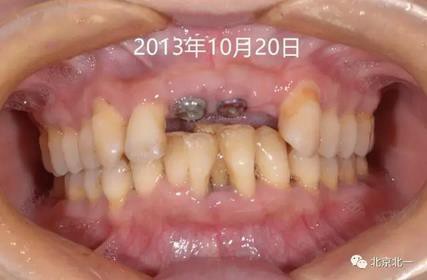

圖四:牙齦袖口,未做牙齦成形。

圖五:戴入基臺,采用粘接固位。

圖六:戴牙后口內(nèi)照,患者笑線低。未做牙齦誘導(dǎo)也不太影響容貌。簡化治療程序節(jié)省患者時間成本以及金錢成本。